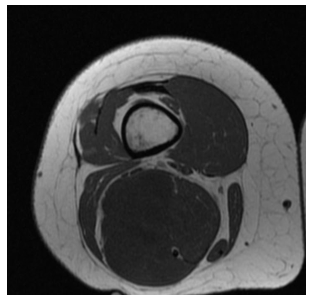

Radiographic imaging is used to help form a diagnosis of pleomorphic liposarcoma. These include X-Ray, MRI, CT and Bone Scans.

An example of an MRI is shown.